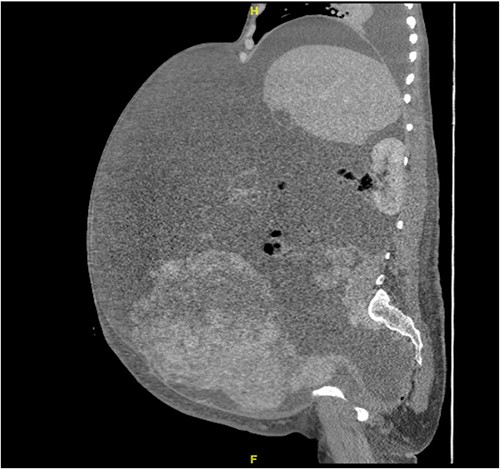

A 40-year-old Saudi, nulliparous woman, medically free with a history of leiomyoma (uterine fibroid) underwent myomectomy. She was referred to our center as a case of large abdominopelvic mass, tense ascites and pleural effusion. The patient complained of the shortness of breath, palpitation, marked abdominal discomfort and bloating as well as back pain. She reported that she first noticed the bloating 3 months prior to the visit. However, she was unable to come because of COVID-19 pandemic situation. She is a housewife; never smoked tobacco or drank alcohol, and had no history of recent travel to endemic or pandemic areas. On further investigations, a serum CA-125 was found to be elevated 492.6 U/mL (normal < 35 U/mL), whereas the concentration of other tumor markers LDH, CEA, CA19-9 and ALP was within normal ranges. Abdominal CT scan revealed a significant interval increase in the size of ascites, which caused a huge abdominal distention along with severe mass effects on the abdominopelvic organs, which have been displaced posteriorly as shown in Fig. 1. In addition, it revealed a large exophytic uterine fibroid measuring 15 × 20 × 17.5 cm. A therapeutic paracentesis was done with the removal of 50.750 ml of ascitic fluid. Figure 2 shows how pleural effusion is markedly significant. A total abdominal hysterectomy, with bilateral salpingo-oophorectomy and omentectomy, was performed. Intraoperative finding revealed a very large mass, which originated from uterine fundus. The pleural effusion and ascites disappeared entirely after the excision of abdominopelvic mass. She recovered completely and went through an uneventful postoperative period. On pathology of surgical specimens, a giant uterine leiomyoma with degenerative changes, pleural and ascitic fluids was yielded negative for malignancy and diagnosed as a benign mesothelial proliferation, whereas H&E stain of the omentum excision surprisingly confirmed multiple, large and irregular disorganized veins (thin-walled blood vessels) and arteries (thick-walled blood vessels), some with organized thrombi consistent with omental AVM as shown in Figs 3 and 4. Provisional diagnosis of pseudo-Meigs’ syndrome with omental AVM was considered.

H&E stain of the omentum excision shows multiple, large and irregular disorganized veins and arteries.